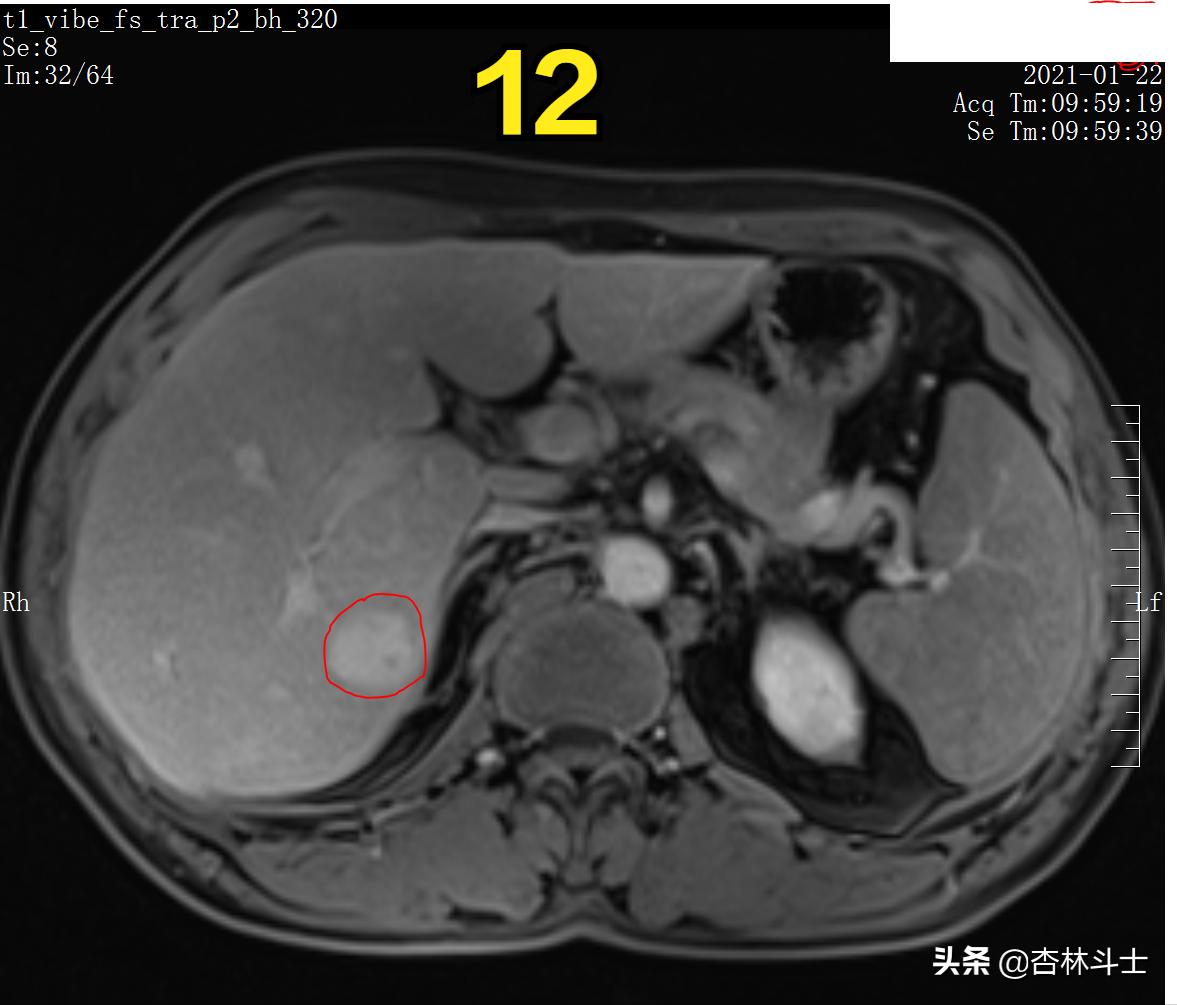

图12 T1加权压脂平衡期

图13 T1加权压脂平衡期

图12-16 持续20余分钟,病灶内仍有特异性对比剂。